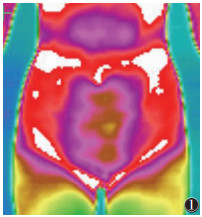

2 结果 2.1 治疗前患者局部代谢热形态根据采集的图像显示,寒湿凝滞型患者的子宫区周边、宫颈区可见明显的细胞代谢热降低区(图 1);代谢热值及热辐射值相对较低,边界清晰,形态较规则,检查过程中可见代谢热从周边向子宫及宫颈区走行(图 2);与两侧腹股沟淋巴联系不密切,且腹股沟淋巴对称,未见明显代谢热差值,下腹部及腰骶部未见异常热源(图 3)。

| 图 1 女,22岁,原发性寒湿凝滞型痛经,子宫区周边、宫颈区可见明显的细胞代谢热降低区 |